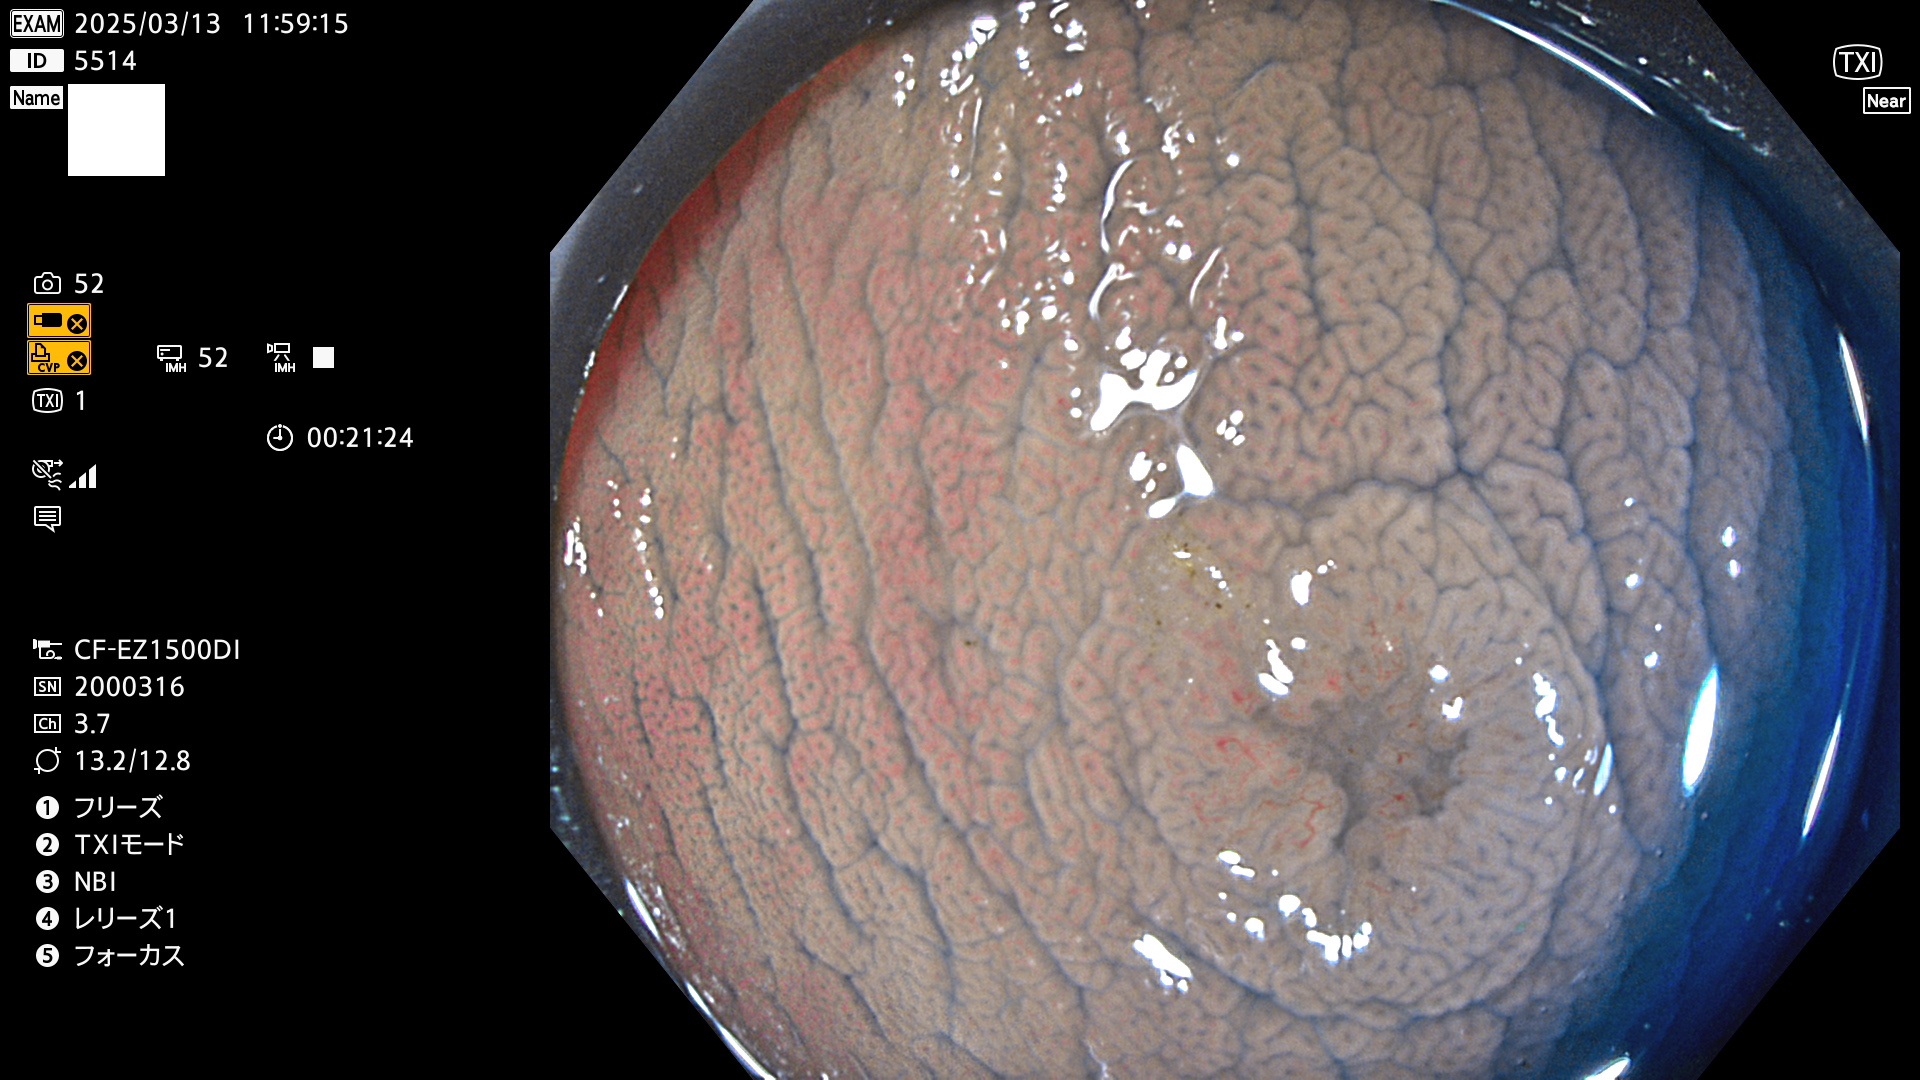

今週のUb、Uc型腺腫

完全に平坦な物をUb、陥凹している物をUcと呼びます。最も発見が難しく危険な病変です。

毎週の検査(木・金・土・日)に発見されたUb、Uc型・腺腫を、その週の日曜の夜にUPし1週間、提示します。

抽出の対象期間 2025年3月13日〜3月16日の4日間(48件の検査)12個 (12/48=25%)